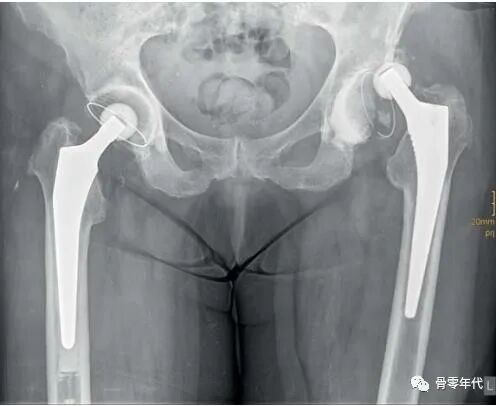

对于复发性脱位的患者,一般应考虑手术翻修的选择。如果出现部件定位错误,则需要进行部件更换。在有肌肉或协调缺陷的患者中,可以使用三极头系统,允许移动的聚乙烯杯在骨锚固窝内和假体头部移动。当假体的颈部与聚乙烯嵌体接触时,这种设计能够通过移动髋臼假体中的嵌体来使关节重新对中。

法国文献报道三极杯系统被成功地用作脱位风险增加的患者的主要治疗方法;然而,由于缺乏足够的磨损行为研究数据和假体内脱位的可能性(头部和嵌体的断开),该方法尚未被普遍采用。在髋关节翻修手术中,这种植入物的缺点是它提供了有限的模块化,并且不允许用螺丝钉加强杯状锚定。由于它们的失败率很高,带有圆形、过半球形头部封闭的约束式嵌体或卡扣式杯子很少使用。